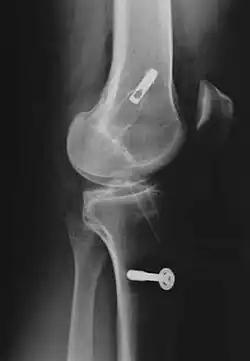

Röntgenaufnahmen leisten keinen unmittelbaren Beitrag zur Diagnosestellung einer Kreuzbandruptur. Beide Kreuzbänder sind – ob gerissen oder nicht – im Röntgenbild nicht sichtbar. Wird dennoch geröntgt, so kann dies der Diagnosestellung von möglichen knöchernen Begleitverletzungen dienen.

Sonderfall knöcherner Ausriss

Der knöcherne Ab- oder Ausriss des vorderen Kreuzbands vom Knochen (Schienbein oder Femur) ist wesentlich seltener als seine intraligamentäre Ruptur[255] und ist definitionsgemäß kein Kreuzbandriss. Dieser Sonderfall tritt häufiger bei Kindern, vor allem im Bereich des Kreuzbandansatzes am Schienbein Eminentia intercondylica auf und hat durch Refixierung des Ausrisses – beispielsweise mit Schrauben oder Drahtnaht – allgemein gute Chancen, wieder vollständig knöchern einzuheilen. Bei der arthroskopischen Refixation der das Kreuzband tragenden Knorpel-Knochen-Schuppe ist eine gute Übersicht von entscheidender Bedeutung, um die Einklemmung des Ligamentum transversum genus (zwischen den Menisken) unter dem Fragment zu vermeiden. Ansonsten ist die Mini-open-Technik vorzuziehen. Generell ist darauf zu achten, mit den Implantaten (Schrauben oder Drahtnähten) die Wachstumsfuge nicht zu blockieren.